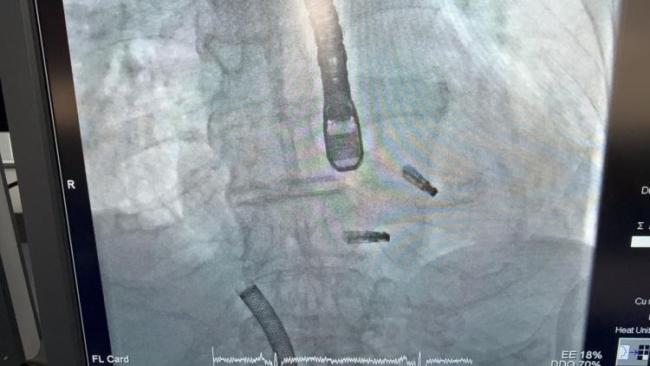

手术由何奔教授主刀,团队成员王建、江立生教授担任助手,麻醉科陆慧红教授、超声专家夏良华及周广为医生密切配合。何奔教授通过股静脉穿刺,经房间隔穿刺置入大鞘,送入夹子,调弯到位,开夹调相,下潜捕捞一气呵成,仅用20多分钟便成功夹住二尖瓣腱索断裂处。心超声显示:二尖瓣反流从重度瞬间降至轻微量。确认安全后,果断释放夹子。随后,大鞘被撤回到右心房,调整方向,对准三尖瓣最大反流处送入一枚更大的夹子,精准夹合。三尖瓣反流从极重度迅速降至轻度。全程仅一个半小时,沪上首例二、三尖瓣“一站式”经皮介入微创修复手术成功完成。术后患者生命体征稳定,恢复良好,3天后步行出院。